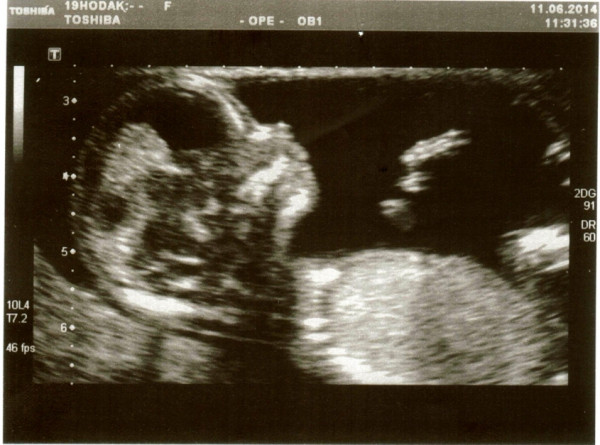

Фото Ребенка 20 Недель

Фото Ребенка 20 Недель 118 фотографий